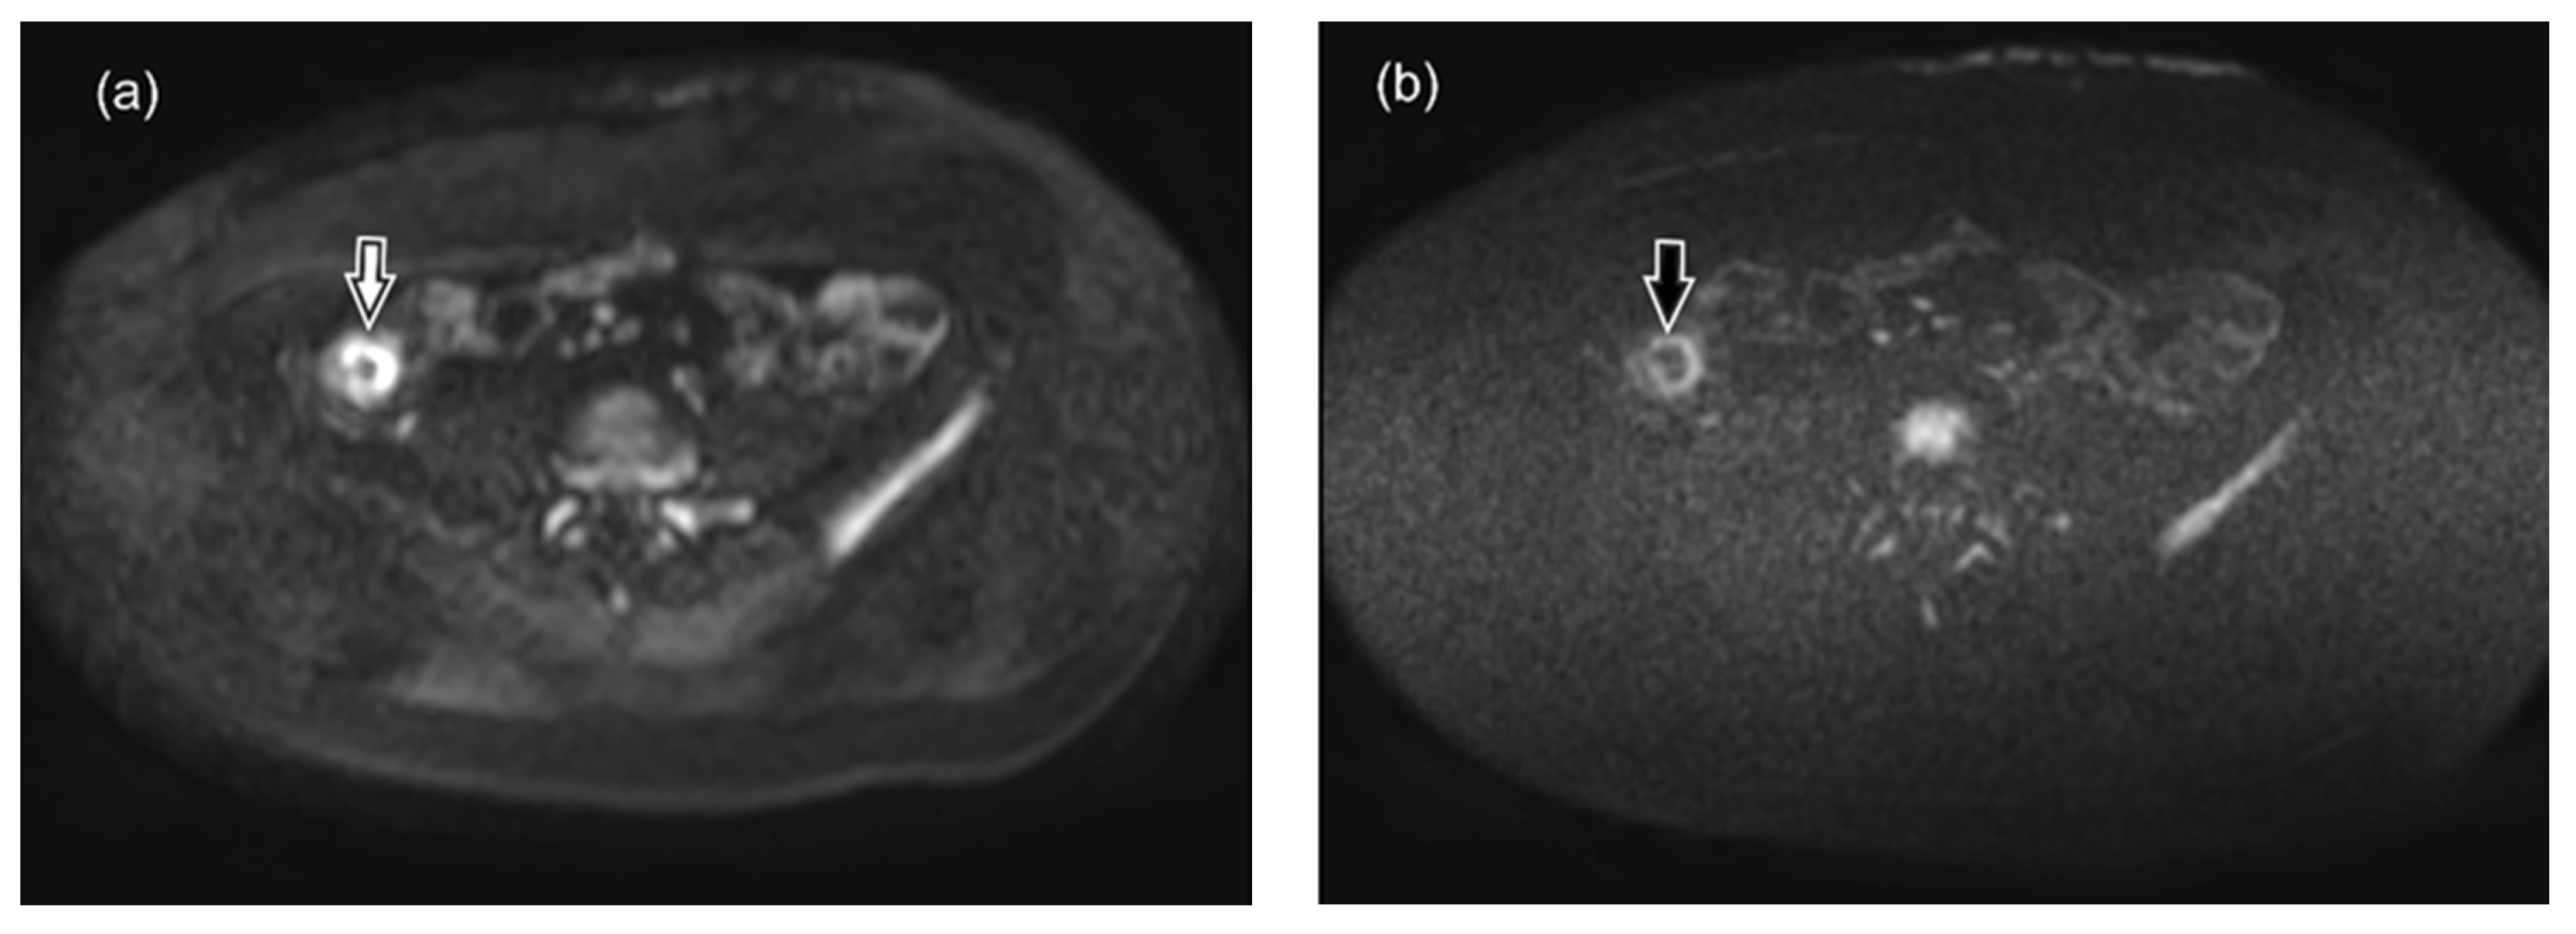

- axial DWI sequence with SPIR, using diffusion factors b fixed at 0, 600 and 800 s/mm2, with corresponding ADC maps,

- axial DWIBS sequence (DWI with STIR), using diffusion factors b fixed at 0, 600 and 800 s/mm2, with corresponding ADC maps,